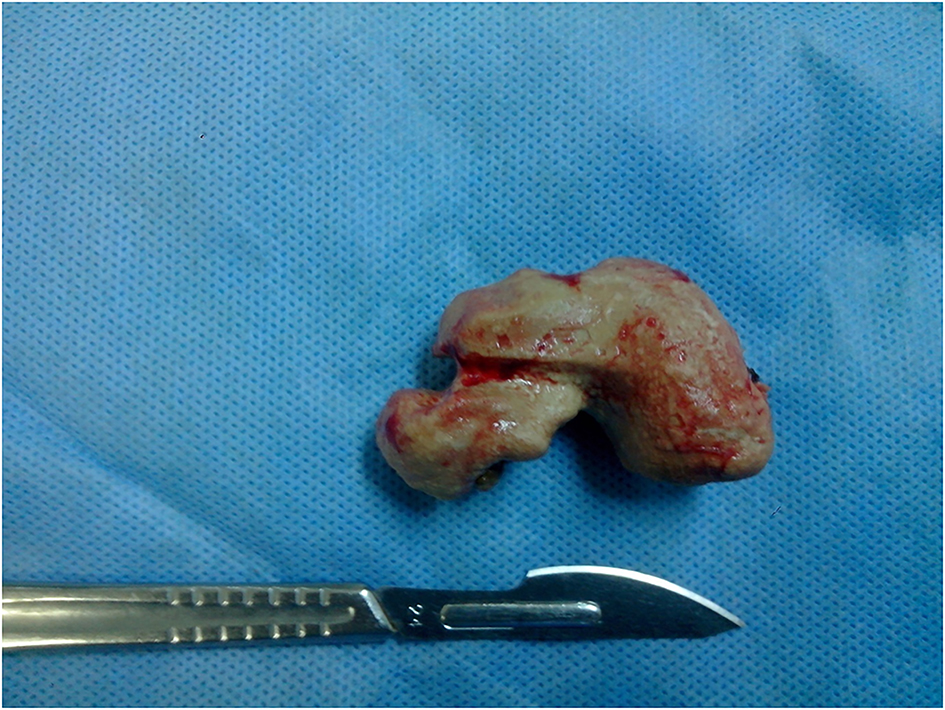

The patient was not compliant and presented again with LUTS, 2 years later. Retrograde cystography was performed and revealed recurrent 5 cm prostatic urethral calculus with a significant post void urine volume, large bladder neck and no evident urethral stenosis (Fig. 2). Complete blood count, renal function, serum parathyroid hormone, and serum calcium levels were within normal limits. An urethrocystoscopy showed normal urethra and a giant prostatic urethral calculus of uniform structure partially located in prostatic urethral diverticulum (Fig. 3). Because of the large stone burden, complete endoscopic removal was not feasible. Therefore, calculus was extracted entirely via cystotomy through bladder neck (Fig. 4). Postoperative plain radiography showed no residual calculus within the urinary tract. Infrared stone analysis revealed that it was composed of calcium phosphates.

![]() Click for large image | Figure 4. Recurrent uniform calculus extracted via cystotomy. |